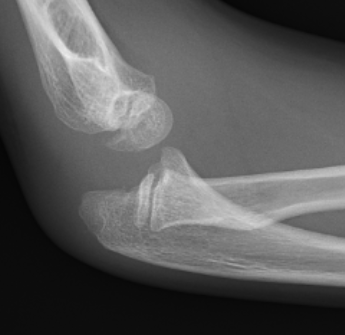

1 year old male: C 5 year old female: CR